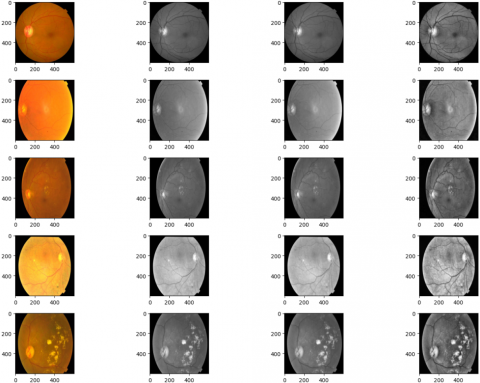

Figure 2. Types of DR based on fundus features

For clearer understanding, refer to the retinal fundus images that represent various phases of DR. Figure 2 displays example images corresponding to the five graded severity levels of DR. Below Table 1. gives the image distribution between 3 benchmark datasets. The decision to use data augmentation led to 60:40 as the training and test split and total number of images was raised to 143,669 and data augmentation was performed exclusively on the training set, with care taken to avoid any overlap with the test samples.